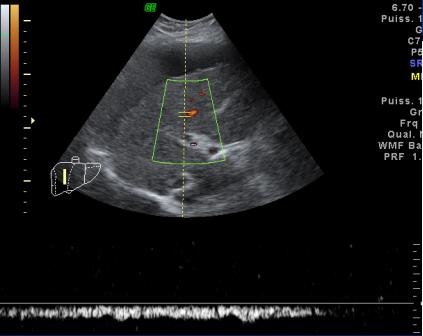

Image echographique Doppler

en couleur d'une steatose du foie marquee: Aspect de

distortion vasculaire intrahepatique |

Steatose du foie marque :

Amortissement du flux sanguine intra-hepatique |